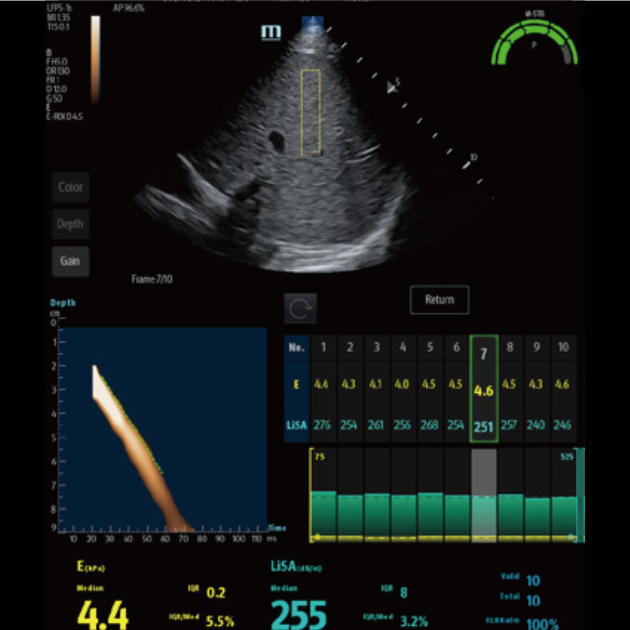

O Hepatus ÃĐ um equipamento de diagnÃģstico profissional n?o invasivo para doen?as hepÃĄticas que fornece resultados quantitativos que indicam o estÃĄgio da fibrose hepÃĄtica. Ele ÃĐ preciso, eficiente, confiÃĄvel e adequado ao acompanhamento de doen?as, abrindo uma nova era para o diagnÃģstico n?o invasivo de doen?as hepÃĄticas.

VÃĄrias solu??es de ultrassom*

â Sonda de ultrassom profissional para facilitar o exame de ascite, etc.

â Pun??o guiada por ultrassom dedicado para aprimorar a precis?o das biÃģpsias

â A excelente qualidade de imagem e as fun??es de ultrassom permitem uma avalia??o abrangente da morfologia e hemodin?mica do fÃgado.